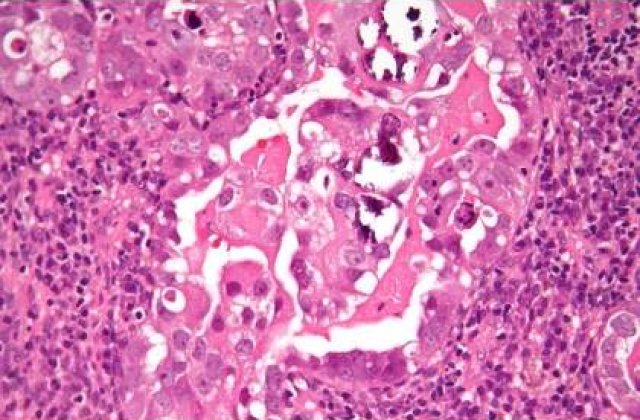

Prevenirea primara acestor cazuri se poate face prin vaccinare, prin care pot fi eliminate cauzele care determina cancerul de col uterin - infectia cu cele mai frecvente tulpini oncogenice (cauzatoare de cancer). Prin vaccinarea anti-HPV a adolescentelor, urmata de testare periodica Babes-Papanicolaou, riscul de cancer de col uterin este redus cu 94%3.